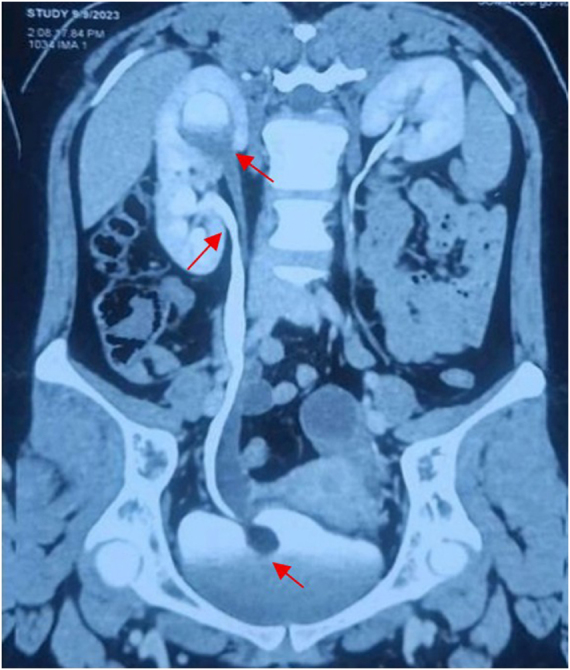

Case presentation: A 23-year-old female presented in a tertiary care hospital with intermittent right flank pain and recurrent UTIs for 3 months. Imaging revealed a right-sided duplex system with an intravesical ureterocele and functioning upper moiety. TFL deroofing was performed, with placement of dual DJ stents. Operative time was 40 minutes with negligible bleeding. Recovery was uneventful, and stents were removed at 6 weeks. At 6 months, imaging confirmed resolved hydronephrosis and preserved function; the patient remained asymptomatic at 12-month tele-follow-up.